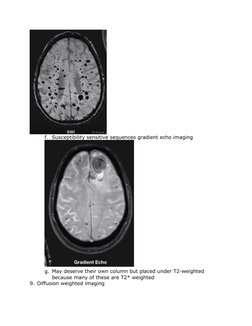

f. Susceptibility sensitive sequences gradient echo imaging

g. May deserve their own column but placed under T2-weighted

because many of these are T2* weighted